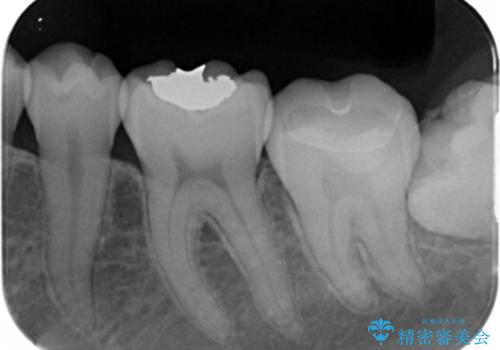

- メタルインレーをセラミックインレーに変えたいとの事で来院。

メタルインレーを外し、拡大鏡下でう蝕がないことを確認して

セラミックインレー(e-maxインレー)にて治療しました。